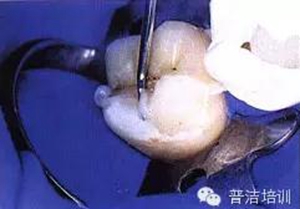

九、準(zhǔn)備口內(nèi)戴入

十、試戴樹脂高嵌體